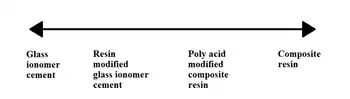

Modern dental sealants generally are either resin based or glass ionomer based.[1]

GIC materials bond both to enamel and dentine after being cleaned with polyacrylic acid conditioner. Some other advantages GICs have is that they contain fluoride and are less moisture sensitive, with suggestions being made that despite having poor retention, they may prevent occlusal caries even after the sealant has fallen out due to their ability to release fluoride.[1][13]

Resin based sealants versus glass ionomer sealants

It was shown that GIC materials were more effective in prevention of development of caries despite the higher non-successful rate compared to resin based sealants.[14] This may be accounted for due to the fluoride-releasing property of GIC which increases salivary fluoride level that may aid in preventing dental caries.

Resin-based sealants are normally the preferred choice of material for denture sealants. GIC material may be used as a provisional protective material when there are concerns regarding adequate moisture control.[15]

On the basis of limited evidence both GIC and resin materials are equally acceptable in caries prevention, however retention rates between GIC and Resin have been shown to differ.[13] Resin has been shown to be the superior product for retention. A 2-year clinical trial comparing GIC and Resin for dental sealants demonstrated that the GIC had a total loss rate of 31.78%, in contrast to the resin which had a total loss rate of 5.96% The study did acknowledge that GIC had its therapeutic advantages other than retention, this included the benefit of fluoride release and its use on partially erupted teeth.[20] Though GIC has poorer retention rates, the fact that they release active fluoride in the surrounding enamel is very important. They can exert a cariostatic effect and increased release of fluoride, and for these reasons GIC is more of a fluoride vehicle rather than a traditional fissure sealant.[21] All three materials are as effective as each other if the correct techniques are used to complete the procedure.[13]